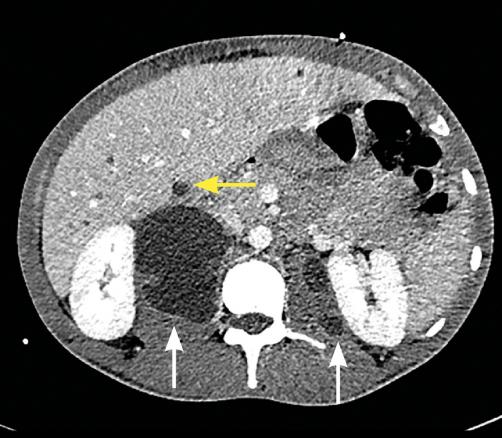

L’imagerie montrait : sur la tomodensitométrie (TDM) thoracique une miliaire tuberculeuse pulmonaire et des adénopathies médiastinales ; sur l’imagerie par résonance magnétique (IRM) du rachis une spondylodiscite T11-T12 (fig. 1 ) ; sur la TDM abdominale des abcès paravertébraux de T9 à T12 le long des psoas (fig. 2 , flèches blanches) et des lésions micronodulaires hépatiques multiples (fig. 2 , flèche jaune) ; sur l’IRM myocardique des signes de péricardite (fig. 3 , flèches). La ponction lombaire montrait une méningite. Un tuberculome était visible sur l’IRM cérébrale, entouré d’un œdème périlésionnel (fig. 4 ). Le diagnostic de tuberculose disséminée était prouvé par polymerase chain reaction sur une ponction d’abcès. Compte tenu de l’atteinte neuroméningée, un traitement adjuvant par corticothérapie s’imposait dans le cas présent, de même qu’une antibiothérapie de 9 à 12 mois.1

L’imagerie montrait : sur la tomodensitométrie (TDM) thoracique une miliaire tuberculeuse pulmonaire et des adénopathies médiastinales ; sur l’imagerie par résonance magnétique (IRM) du rachis une spondylodiscite T11-T12 (